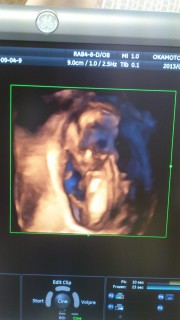

体外受精で授かりました。 82.4㎜で順調だそうです(^^) 4Dエコーでは、顔立ちがはっきり見えてきました♪ マタニティヨガやビクスの教室にも参加OKと言われました♪